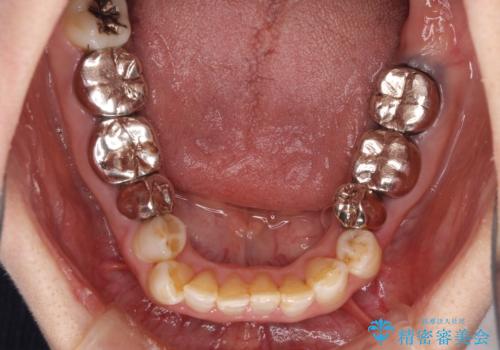

- 全顎的な歯列不正と、銀歯だらけの奥歯を気にして来院された患者様です。

奥歯の銀歯は、セラミッククラウンを装着するには歯の高さが不十分であり、そのままでは矯正治療を行うことが困難であるため、歯冠長延長術を行うこととしました。

また、根管治療の必要な歯がいくつかあるため、歯周外科治療の治癒期間を利用して根管治療を行い、その後インビザラインにて矯正治療を行うこととしました。